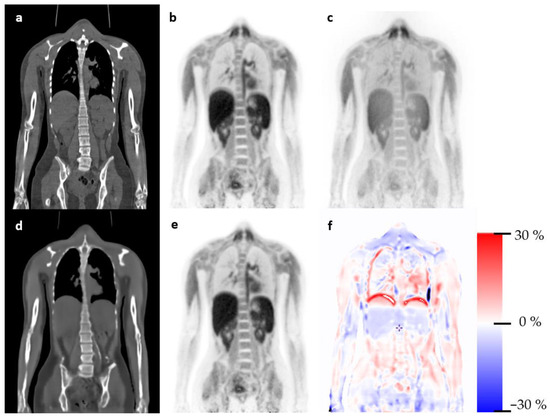

3.1. Qualitative Evaluation

3.2. Quantitative Evaluation